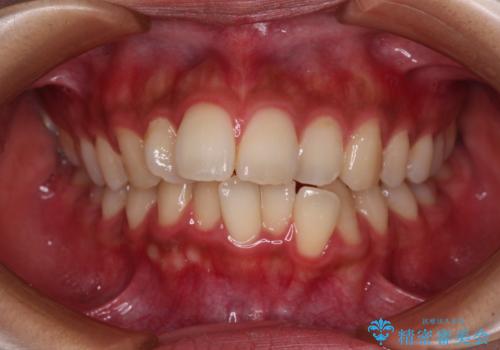

[前歯のねじれ 部分]ワイヤーとマウスピースの併用矯正治療

担当医 大元洋佑